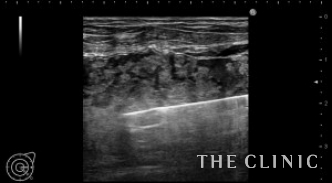

右)カニューレで壊死した脂肪を吸引除去します。